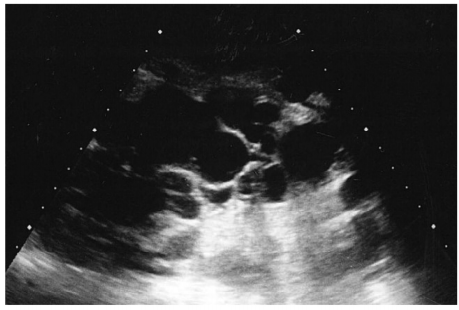

44 32 歳の女性。腹部膨満感を主訴に来院した。母親が慢性腎不全で血液透析を受 けている。両側季肋部から両側側腹部に腫瘤を触知し、軽度の圧痛を認める。血圧 146/92 mmHg。尿所見:蛋白案、潜血 安。血液生化学所見:尿素窒素 20 mg/dL、クレアチニン 1.2 mg/dL。左の側腹部の腹部超音波像別冊No. 8Aと腹 部 CT の冠状断像別冊No. 8Bとを別に示す。 次に行うべき検査はどれか。 (A)腎生検 (B) 頭部 MRA (C)排泄性尿路造影 (D) 下部消化管内視鏡 (E)ガリウムシンチグラフィ